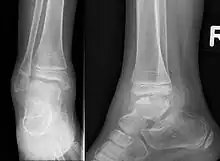

This disorder is rare, and is characterised by an asymmetrical limb deformity due to localized overgrowth of cartilage, histologically resembling osteochondroma. It is believed to affect the limb bud in early fetal life. The condition occurs mostly in the ankle or knee region and it is always confined to a single limb. This usually involves only the lower extremities and on medial side of the epiphysis. It is named after researcher David Trevor.[1]

Trevor disease was first described by the French surgeon Albert Mouchet and J. Belot in 1926. In 1956, the name "dysplasia epiphysealis hemimelica" was proposed by Fairbank.[1] The usual symptoms are the appearance of an osseous protuberance, on one side of the knee, ankle or foot joint which gradually increases Radiologically,[14] the condition shows a nonuniformity of growth and multiple unconnected ossification centers around the epiphyses.[8]